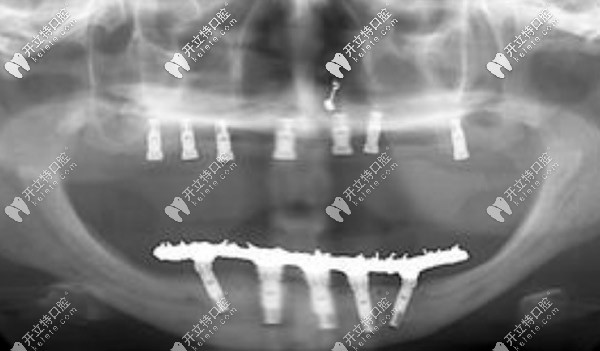

【全口allon4/6即刻負(fù)重技術(shù)】

一般需要8顆或12顆種植體,可恢復(fù)全口牙,當(dāng)然這個(gè)費(fèi)用比較高,韓系的價(jià)格一般在12萬(wàn)元起

滿口allon4/6即刻負(fù)重技術(shù)

種植牙的優(yōu)勢(shì)就不過(guò)多介紹了,ALLon4與普通的種植技術(shù)不同在于,利用斜拉式的力學(xué)原理,可以避免上頜竇及下頜神經(jīng)等危險(xiǎn)區(qū),當(dāng)天即可戴牙吃東西。美中不足則是該技術(shù)對(duì)醫(yī)生的技術(shù)要求較高,且費(fèi)用較高。